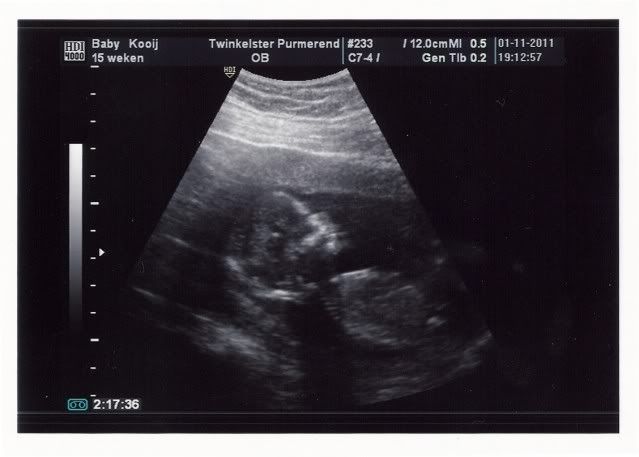

En het wordt een????

En het wordt een???

Eerst wilde hij het niet laten zien en hield hij zijn handje precies voor zijn piep hahah maar al snel werd zijn geslacht zichtbaar! We krijgen een jongen!! :D